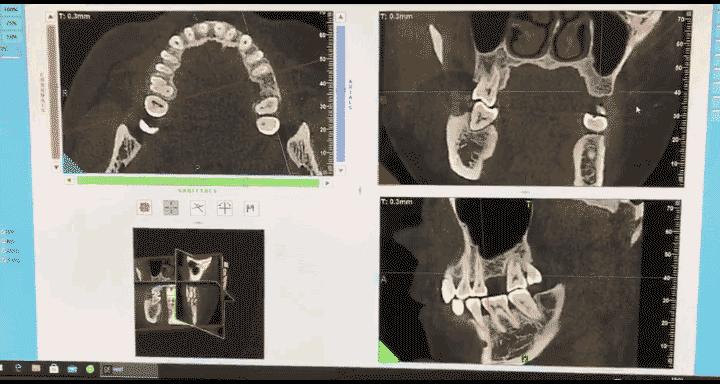

5、导致牙槽骨萎缩

牙齿长期缺失,失去了正常咬颌力对牙槽骨的生理性刺激,那么就容易出现废用性萎缩,到了后期,想要进行缺牙修复都会存在较高的难度。